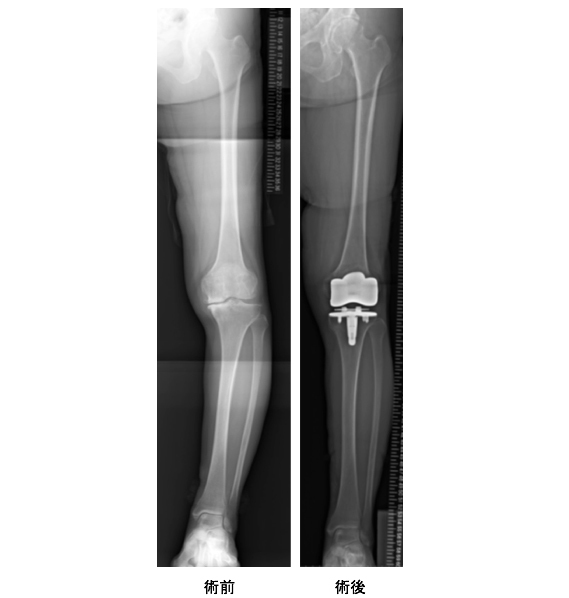

人工関節置換術は、その名の通り関節を人工物に置き換える手術です。人工関節には、膝全体の関節を取り替える全置換術と膝の内側や外側など一部だけ取り替える単顆置換術があります。患者さんの希望にもよりますが、基本的には人工関節の手術を受ける患者さんは、病気がかなり進行している方です。変形性膝関節症の末期の状態で、たとえば骨まで削れてしまったり、膝関節の動きが極めて悪くなってしまったり、または全型の膝関節症になってしまった患者さんに適応されることが多いです。お話ししたような膝周囲骨切り術では治療が難しい場合に実施され、手術後は日常生活を問題なく送ることができます。しかし、人工関節の手術後は、膝の曲げ伸ばしをスムーズに行えるようにするリハビリも大変です。患者さんの年齢や状態にもよりますが、術後はスポーツや重労働は避けなければならず、正座をすることがほとんどの場合困難です。体に負担が大きい手術であるため、実施には十分な検討が必要でしょう。

AKO(膝周囲骨切り術)と並び、変形性膝関節症の患者さんに適応されることが多い手術が人工関節に置き換える人工関節置換術です。私たちさいわい鶴見病院では、関節を全て入れ替える人工関節全置換術を採用していますが、これは患者さんの負担が大きな手術になります。